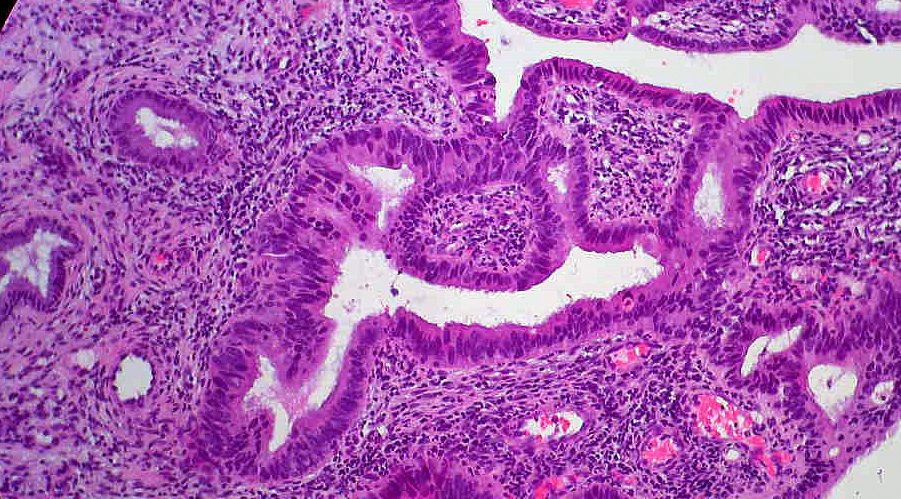

Visualizan las metástasis del melanoma antes de que ocurran e identifican nuevas dianas para su tratamiento